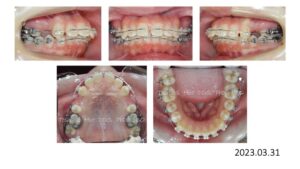

治療終了時の写真です。

動的治療期間は、1年 5か月です。

上顎前歯は 8㎜、下顎前歯は 4㎜後退し、口が閉じれないという主訴も改善されました。